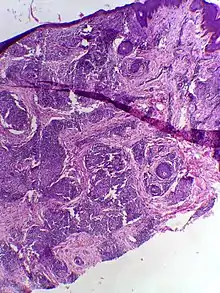

![]() | Squamous cell carcinoma of the skin | Well-differentiated squamous cell carcinoma skin showing malignant cells with mild atypia resembling normal squamous epithelial cells with intercellular bridges, individual cell keratinisation and nests of keratin pearls. | Category: Histopathology of squamous cell carcinoma of the skin | Squamous cell carcinoma |